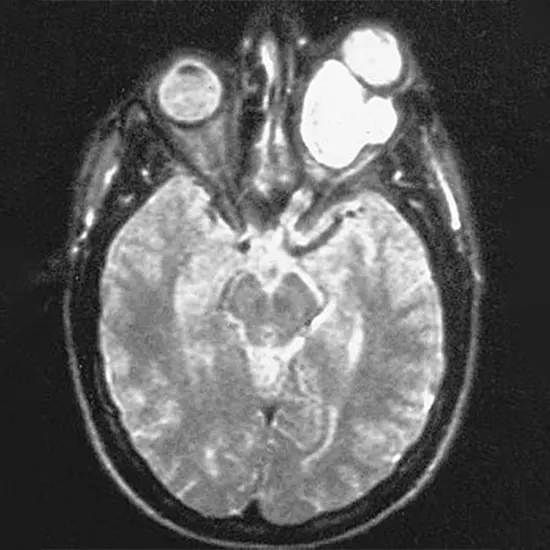

Magnetic resonance imaging scans

Often reveal enlargement, kinking, and buckling of the optic nerve. The nerve is enlarged and fusiform in shape because of the attachment of the investing dura to the periosteum of the optic canal. MRI brain scan may exhibit cystic degeneration if present.MRI is useful in showing intracranial extension.